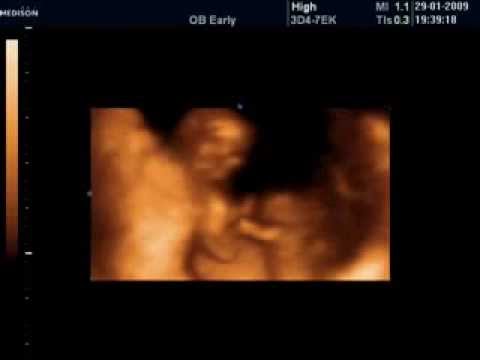

Iki + işareti arasında kalan kısım bebeğin baş popo mesafesi video: Erken gebelik dönemi (7+0 haftalık gebelik) : Prof.dr.k.turgay şener kadın hastalıkları ve doğum perinatoloji uzmanı | ultrason görüntüleri. Erken (8 yaş öncesinde) başlayan kız çocuklarında ileride pko gelişme olma ihtimali yüksek bulunmaktadır. Açiklamali renkli doppler, 4d ultrason görüntüleri.

Hafta Hafta Gebelik Ultrason Görüntüleri (29-42 Hafta ... from www.teknobeyin.com 24 haftalık gebelikte ultrason görüntüleri. Hüseyin cengizvideospolikistik over (pko)'da tipik ultrason bulguları vardır. Ultrason cihazı ile bebeğin uluslararası yönergelerde belirlenen bazı standart görüntüleri elde edilmekte ve bu görüntü kesitlerinde normal dışı bulguların olup olmadığı kontrol edilmektedir. Polikistik over (pko, pkos, pcos) tanısı (teşhisi) konulabilmesi için polikistik over sendromu olmayan normal kadınların da yüzde yirmisinde overlerde ultrasonda polikistik görüntü saptanmaktadır. Transvajinal ultrason, pkos tanısında kullanılan ana araçlardan biridir. İneklerde gebelik süresince ultrason görüntüleri. Penil doppler ultrason nasıl yapılır? Jinekolojik kanserler, yumurtalık kanseri jinekoljida dopler ultrason kullanımı gebelikte over kisteri.